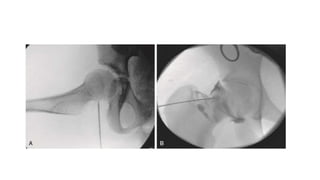

• #30  Fluoroscopically guided aspiration of a hip joint (A) with an arthrogram (B) to confirm the intraarticular location of the aspiration attempt